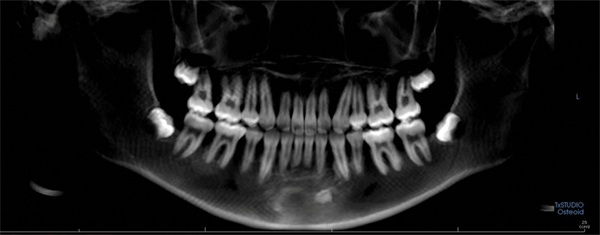

Pretreatment records included extraoral and intraoral photographs, a panoramic radiograph, and a lateral cephalometric radiograph. The panoramic radiograph showed the permanent dentition with no obvious generalized pathology and acceptable root form before treatment (Fig. 2). The dentition was otherwise suitable for comprehensive orthodontic treatment.

Fig. 2